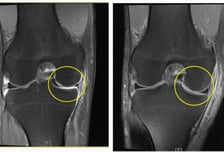

괜찮아지겠지?…무릎서 "사각사각" 연골의 '비명'

#. 서울 강북구에 사는 김모 씨(49세)는 얼마 전 봄을 만끽하려 산을 오르던 중, 가볍게 넘어져 무릎을 다쳤다. '괜찮겠지' 하는 심정으로 집에서 찜질하며 쉬었지만, 통증이 가라앉지 않아 병원을 찾았다. 문진 후 영상 검사를 받은 김 씨의 진단명은 '반월상 연골 파열'. 무릎을 굽히고 펴는 동작이 불편하고, 통증이 심해 잠을 제대로 이룰 수 없던 김 씨는 반월상 연골판이 찢어져 있고 손상 부위가 커서 결국 수술받았다. 다소 생소한 이름의 반월상(반달 모양) 연골판은 허벅지 뼈와 정강이뼈 사이를 잇는 무릎 조직으로, 충격을 흡수할 뿐 아니라 연골의 접촉면을 넓혀 관절을 잘 움직이게 하는 역할을 한다. 스포츠 외상, 사고처럼 큰 충격을 받으면 손상당할 수 있다. 찢어진 연골판 조각이 관절 사이 껴 관절의 움직임을 방해하고 통증과 함께 무릎이 굽혀지지도 펴지지도 않는 잠김 현상이 나타나 환자들이 불편함을 크게 느끼기도 한다. 초기에는 무릎의 힘이 빠지는 느낌과 함께 쪼그려 앉았다가 일